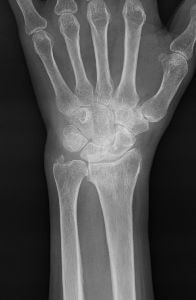

橈骨遠位端骨折と橈骨遠位端変形治癒骨折

橈骨遠位端関節内粉砕骨折の術前(上)と術後(下)

橈骨遠位端骨折は、通年ですべての年齢層において最も多い上肢の骨折の一つです。骨折の主な原因は、転倒や高所から転落して手をつくことですが、手を強く捻って受傷することもあります。本骨折は、ケガの仕方、外力の大きさや骨の強さにより折れる場所や折れ方に様々なタイプ(型)があるのが特徴であり、尺骨や手根骨の骨折、手関節の靭帯損傷や神経障害を合併することもあります。

治療法は、骨折の型、骨折の徒手整復の可否、そして合併症の有無により異なり、比較的軽いものには保存的治療が、変形が大きかったり粉砕していたり骨折が関節内に及ぶ重症例には手術が行われてきました。しかしながら、近年は一人暮らしのご高齢の方の増加により、さほど重症でない骨折に対しても、早期から手の使用を可能とし、後遺障害を少なくするために手術を行うことが多くなってきています。

手術には、経皮的に鋼線を刺入して固定するピンニングや骨折部を直視下に整復してプレート固定する観血的手術があります。術後には早期の機能回復を目的としてリハビリ(作業療法)を行うことがあります。

大きな変形を残して骨が癒合すると手関節の疼痛や手指の機能障害が残存したり、将来、二次性の変形性関節症を生じる原因となることがあります。骨の変形による症状を改善させるために、矯正手術(骨切術)が必要になることがあります。

『骨折したのだから障害が残っても仕方が無い』という考え方は過去のものです。将来なるべく不自由をしないために、きちんとした診断と適切な治療を受けられて下さい。新鮮な骨折はもちろん骨折後の障害についても、お気軽にご相談下さい!